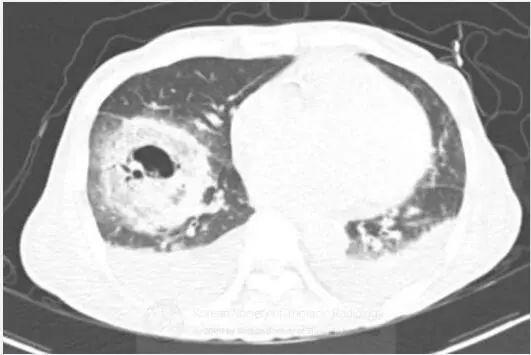

图1胸片示右肺下叶空洞性实变和左肺下叶实变。CT示右肺下叶类圆形实变伴中央磨玻璃影(反晕征),和空洞性病变。可见双侧胸腔积液。